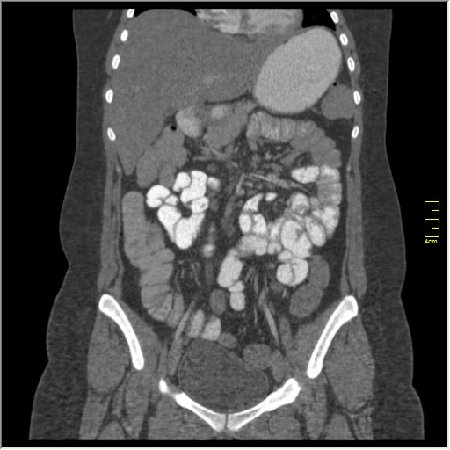

КТ энтерография

Демонстрационные изображение, оцените возможности метода! Толщина среза реконструкции 0.5-1 мм.